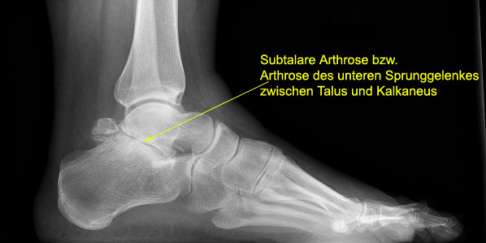

Die bildgebende Untersuchung: Röntgen, Ultraschall und MRT

Subtalare Arthrose im Röntgenbild:

- Schmaler oder aufgehobener Gelenkspalt.

- Osteophyten (Knochensporne) am Rand der Fußgelenke.

- Subchondrale Skelerosierung (Verdichtung) der Knochen unter dem Knorpel).

- Knochenzysten unter dem Gelenkknorpel.

Da die Arthrose einen Verlust des Knorpelüberzugs der Gelenkflächen aufweist, kann mittels bildgebender Verfahren (Röntgen, CT, MRT) eine Verengung des Gelenkspaltes nachgewiesen werden. Wir führen hier stets Röntgenbilder unter Belastung beider Füße durch. Die beidseitige Ansicht im Röntgenbild ist wichtig, um unterschiedliche Entwicklung der beiden Füße und Sprunggelenke im Vergleich zeigen zu können.